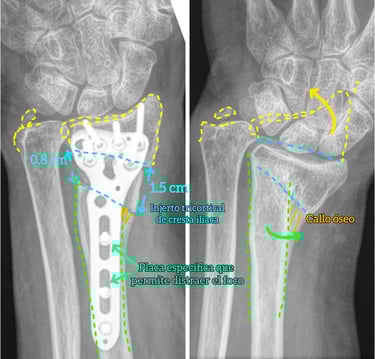

Osteotomías correctoras con planificación 3D

Transferencias nerviosas y tendinosas

Artrodesis totales o parciales

Especialistas en cirugía prótesica

Tratamiento de secuelas y casos complejos